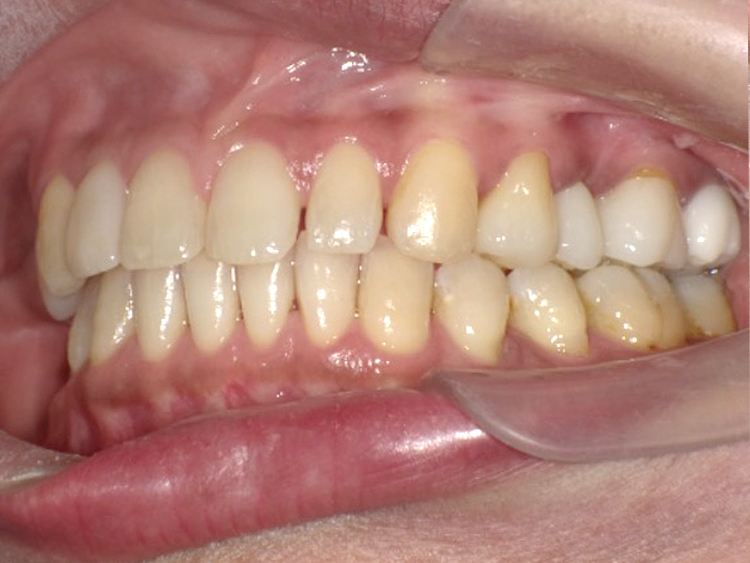

症例3

Before

After

| 主訴 | 上下の歯のガタガタを治したい |

|---|---|

| 年齢 | --- |

| 治療期間 | 約10ヶ月 |

| 治療内容 | インビザラインiGoで上下顎の治療。 狭まっていた歯並びを広げることで、 ガタガタに並んでいた歯を綺麗に並べた。 |

| 治療費 | ¥517,000(税込)+月額調整料 |

| 治療のリスク | 歯と歯の間を削ることでスペースを確保するので、 場合によっては歯が染みる症状が出ることがある。 |